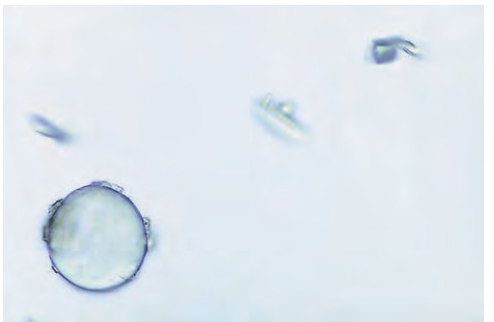

<p><span style="font-family: MyriadPro-Light;">Air bubble</span></p>

Air bubble